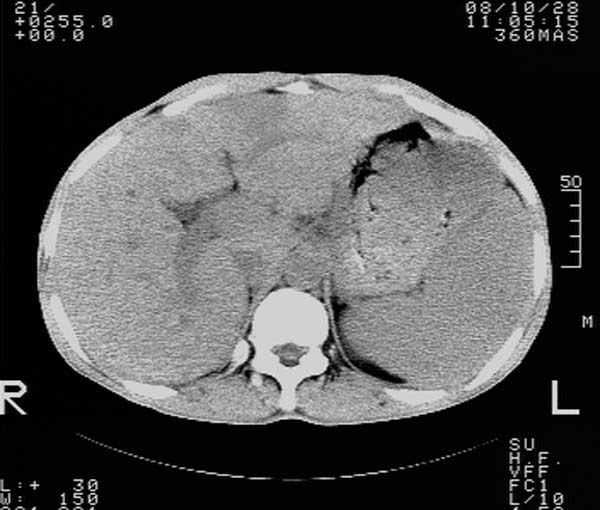

m,65y。半年前发现颈小结节,逐渐增多增大,现双侧耳后、颌下及颈部表浅淋巴肿大。胸片示双肺门增大。外院曾穿刺诊断为淋巴结核。在我科作胸腹部ct,我们觉得外院病检有误。现将图像上传请战友讨论。

纵隔内及腹膜后广泛淋巴结肿大,脾大,肝内似可见低密度影,结合病史半年前发现颈小结节,逐渐增多增大,现双侧耳后、颌下及颈部表浅淋巴肿大。考虑淋巴瘤。

我们也是首先考虑淋巴瘤。只是外院病检报告是结核。让人迷惑。肝左叶多发低密度占位,没增强不好定论。

纵隔,双肺门腹膜后多发淋巴结重大,非融合,肝脾轻度肿大,双肺野弥漫性小结节;考虑淋巴瘤,结节病可能性

纵隔内,双肺门、腋窝及腹膜后多发肿大淋巴结影,肺内小结节影,肝脾体积增大,支持淋巴瘤。肝内多发低密度影,考虑小囊肿。

考虑淋巴瘤肺、肝内转移,脾脏肿大。

纵隔内,双肺门、腹膜后多发肿大淋巴结影及颈部淋巴结肿大,肝脾体积大.结合临床,淋巴瘤可能性大。